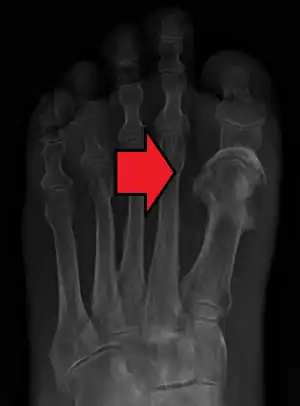

Radiographs and CT are the initial method of diagnosis, but are not sensitive and only moderately specific for the diagnosis. They can show the cortical destruction of advanced osteomyelitis, but can miss nascent or indolent diagnoses.[20]

Confirmation is most often by MRI. The presence of edema, diagnosed as increased signal on T2 sequences, is sensitive, but not specific, as edema can occur in reaction to adjacent cellulitis. Confirmation of bony marrow and cortical destruction by viewing the T1 sequences significantly increases specificity. The administration of intravenous gadolinium-based contrast enhances specificity further. In certain situations, such as severe Charcot arthropathy, diagnosis with MRI is still difficult.[20] Similarly, it is limited in distinguishing bone infarcts from osteomyelitis in sickle cell anemia.[21]

Diagnosis of osteomyelitis is often based on radiologic results showing a lytic center with a ring of sclerosis.[10] Culture of material taken from a bone biopsy is needed to identify the specific pathogen;[23] alternative sampling methods such as needle puncture or surface swabs are easier to perform, but do not produce reliable results.[24][25]